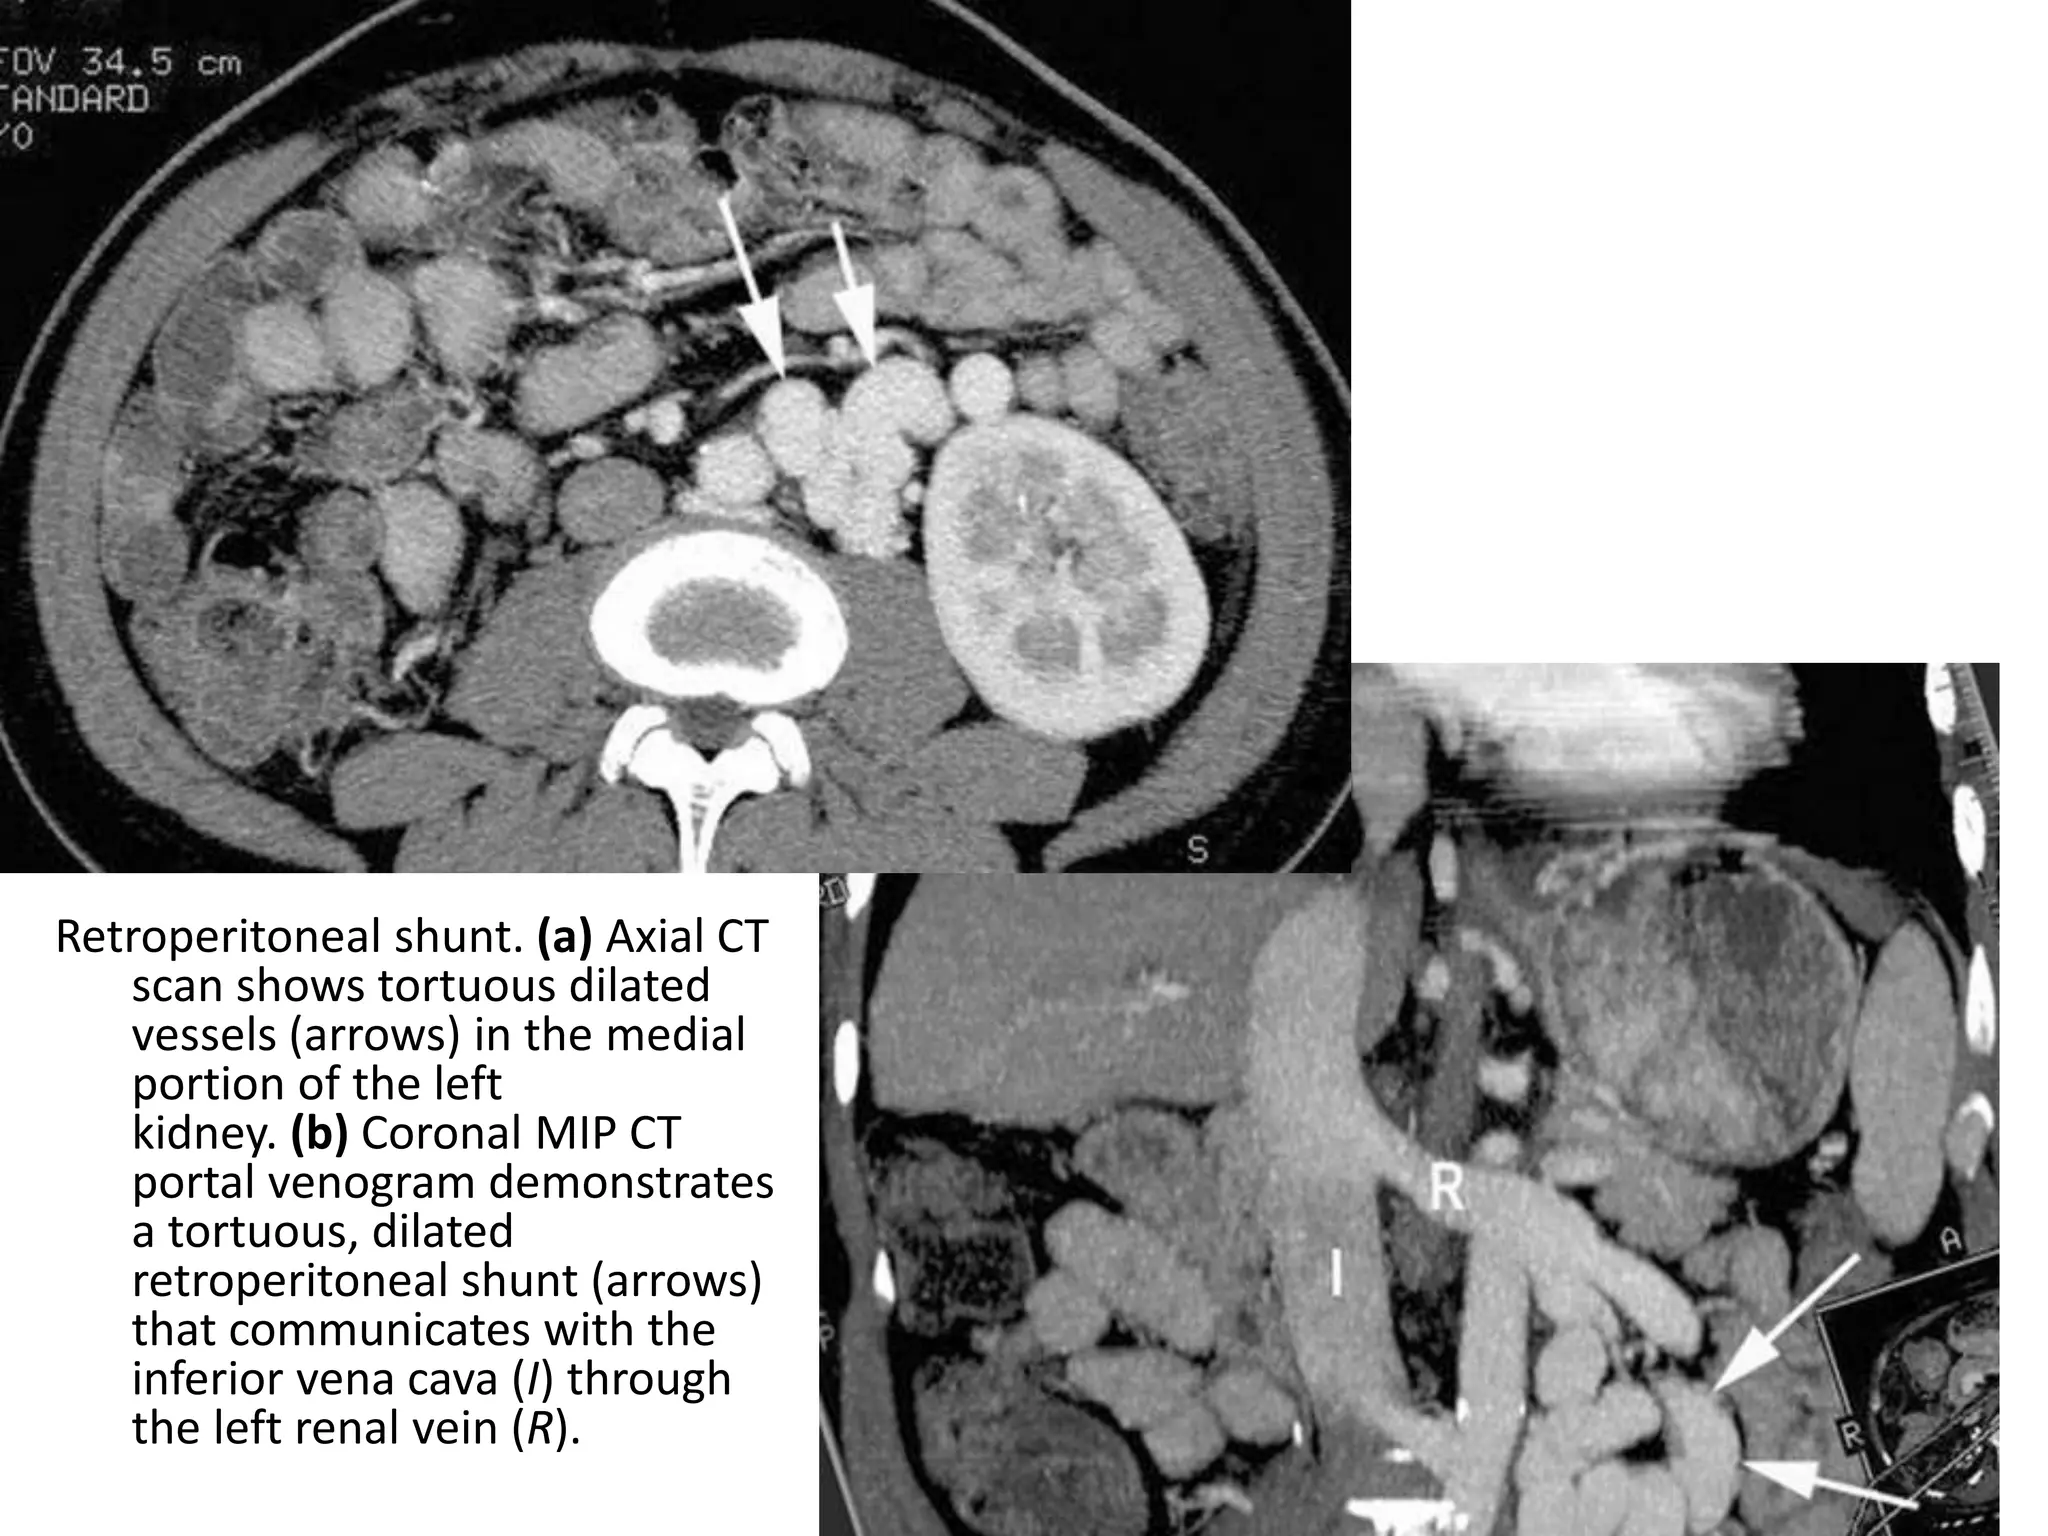

Retroperitoneal shunt. (a) Axial CT

scan shows tortuous dilated

vessels (arrows) in the medial

portion of the left

kidney. (b) Coronal MIP CT

portal venogram demonstrates

a tortuous, dilated

retroperitoneal shunt (arrows)

that communicates with the

inferior vena cava (I) through

the left renal vein (R).